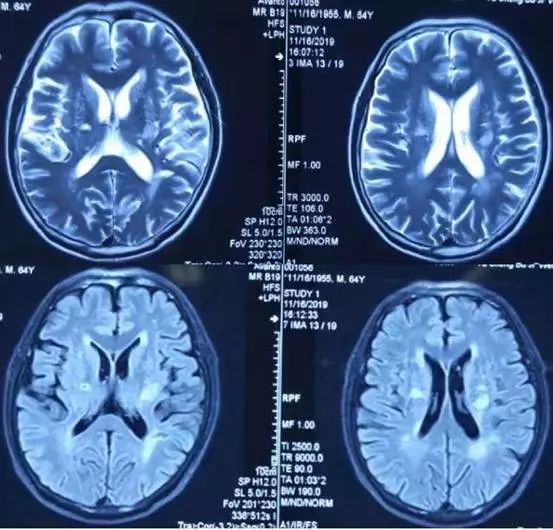

病例7

52岁,男性,头晕20余天,伴言语不利、智能下降。患者自述于20余天前无明显诱因下出现头晕,呈持续性头重脚轻感,无明显规律,伴有言语欠流利、智能下降,表现为计算力、理解力、记忆力下降,偶有咳嗽、呈阵发性单声咳,咳少许白色粘痰;间断发热,最高体温38.5℃。影像学如下:

影像学可见双侧颞、顶叶及右侧额叶多发散在皮层下白质病变,长T2,DWI高信号,ADC高信号。疾控中心HIV-1抗体:阳性,CD4+64cell/ul。

诊断: HIV相关脑病(HIV相关痴呆)

病例讨论:

根据当前针对HIV相关神经认知障碍(HIV-associated neurocognitive disorder,HAND)的国际“Frascati”分类标准,可分为无症状性(ANI),轻度认知障碍(MND)和HIV痴呆(HAD)三个阶段。ANI为量表提示有认知域损害,但日常生活能力无影响;MND轻度的认知功能障碍且影响日常生活能力轻度受损;HAD为明显认知障碍且日常生活能力明显受损。(Neurology. 2007 Oct 30; 69(18):1789-99.)

艾滋病相关性痴呆在 20% 的 AIDS患者中发生,往往是HIV感染缓慢进展数月后出现的迟发表现,这类患者CD4+细胞>350/μl。

HIV相关痴呆与 “皮质型”痴呆如阿尔茨海默不同,前者较少出现失写、失算、失用等皮质功能障碍。一些研究者称其为皮质下痴呆,表现为短期记忆和执行功能损伤。

脑部 MRI 显示萎缩和广泛白质改变。运动障碍也可单独发生或伴随 HIV引起的痴呆一同发生发展。HIV 感染者中运动障碍的发生率为 3%。

其影像学表现常位于白质,如脑室旁、半卵圆中心,呈对称、弥漫、云雾样白质异常,病灶可延伸至灰白质交界处。

看两例文献图:

Case1:

Case2:

图自:Topics in Magnetic Resonance Imaging .Volume 23, Number 5, October 2014

回到该病例,无论临床及影像学,除需要进一步完善认知功能评估之外,尚需要与进行性多灶性白质脑病(PML)相鉴别。PML是由JC病毒侵犯免疫抑制的HIV患者导致的中枢神经系统感染。影像学特点是以顶叶为主的皮层下白质散在受累,并呈融合趋势,会累及U形纤维是其特点之一。